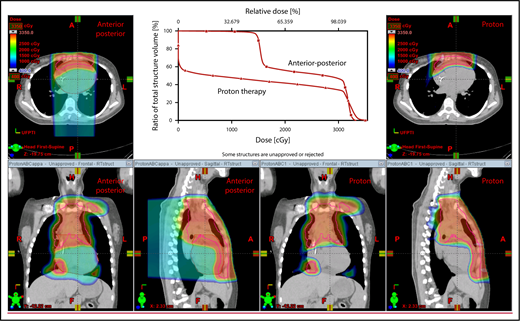

An example of an approach using 2 anterior fields with proton therapy, which can better spare the heart and esophagus (right) compared with an anterior/posterior approach (left).

Plans for PBSPT with a single-field uniform dose and a gradient match, with anterior and posterior beams used to treat disease that involves the bilateral upper neck and the mediastinum (disease anterior to the right heart).

Scans for a young woman in whom the target included mediastinal, left parasternal, and left axillary regions. One anterior field was used for the mediastinum, and a separate posterior field was used for the axillary region.